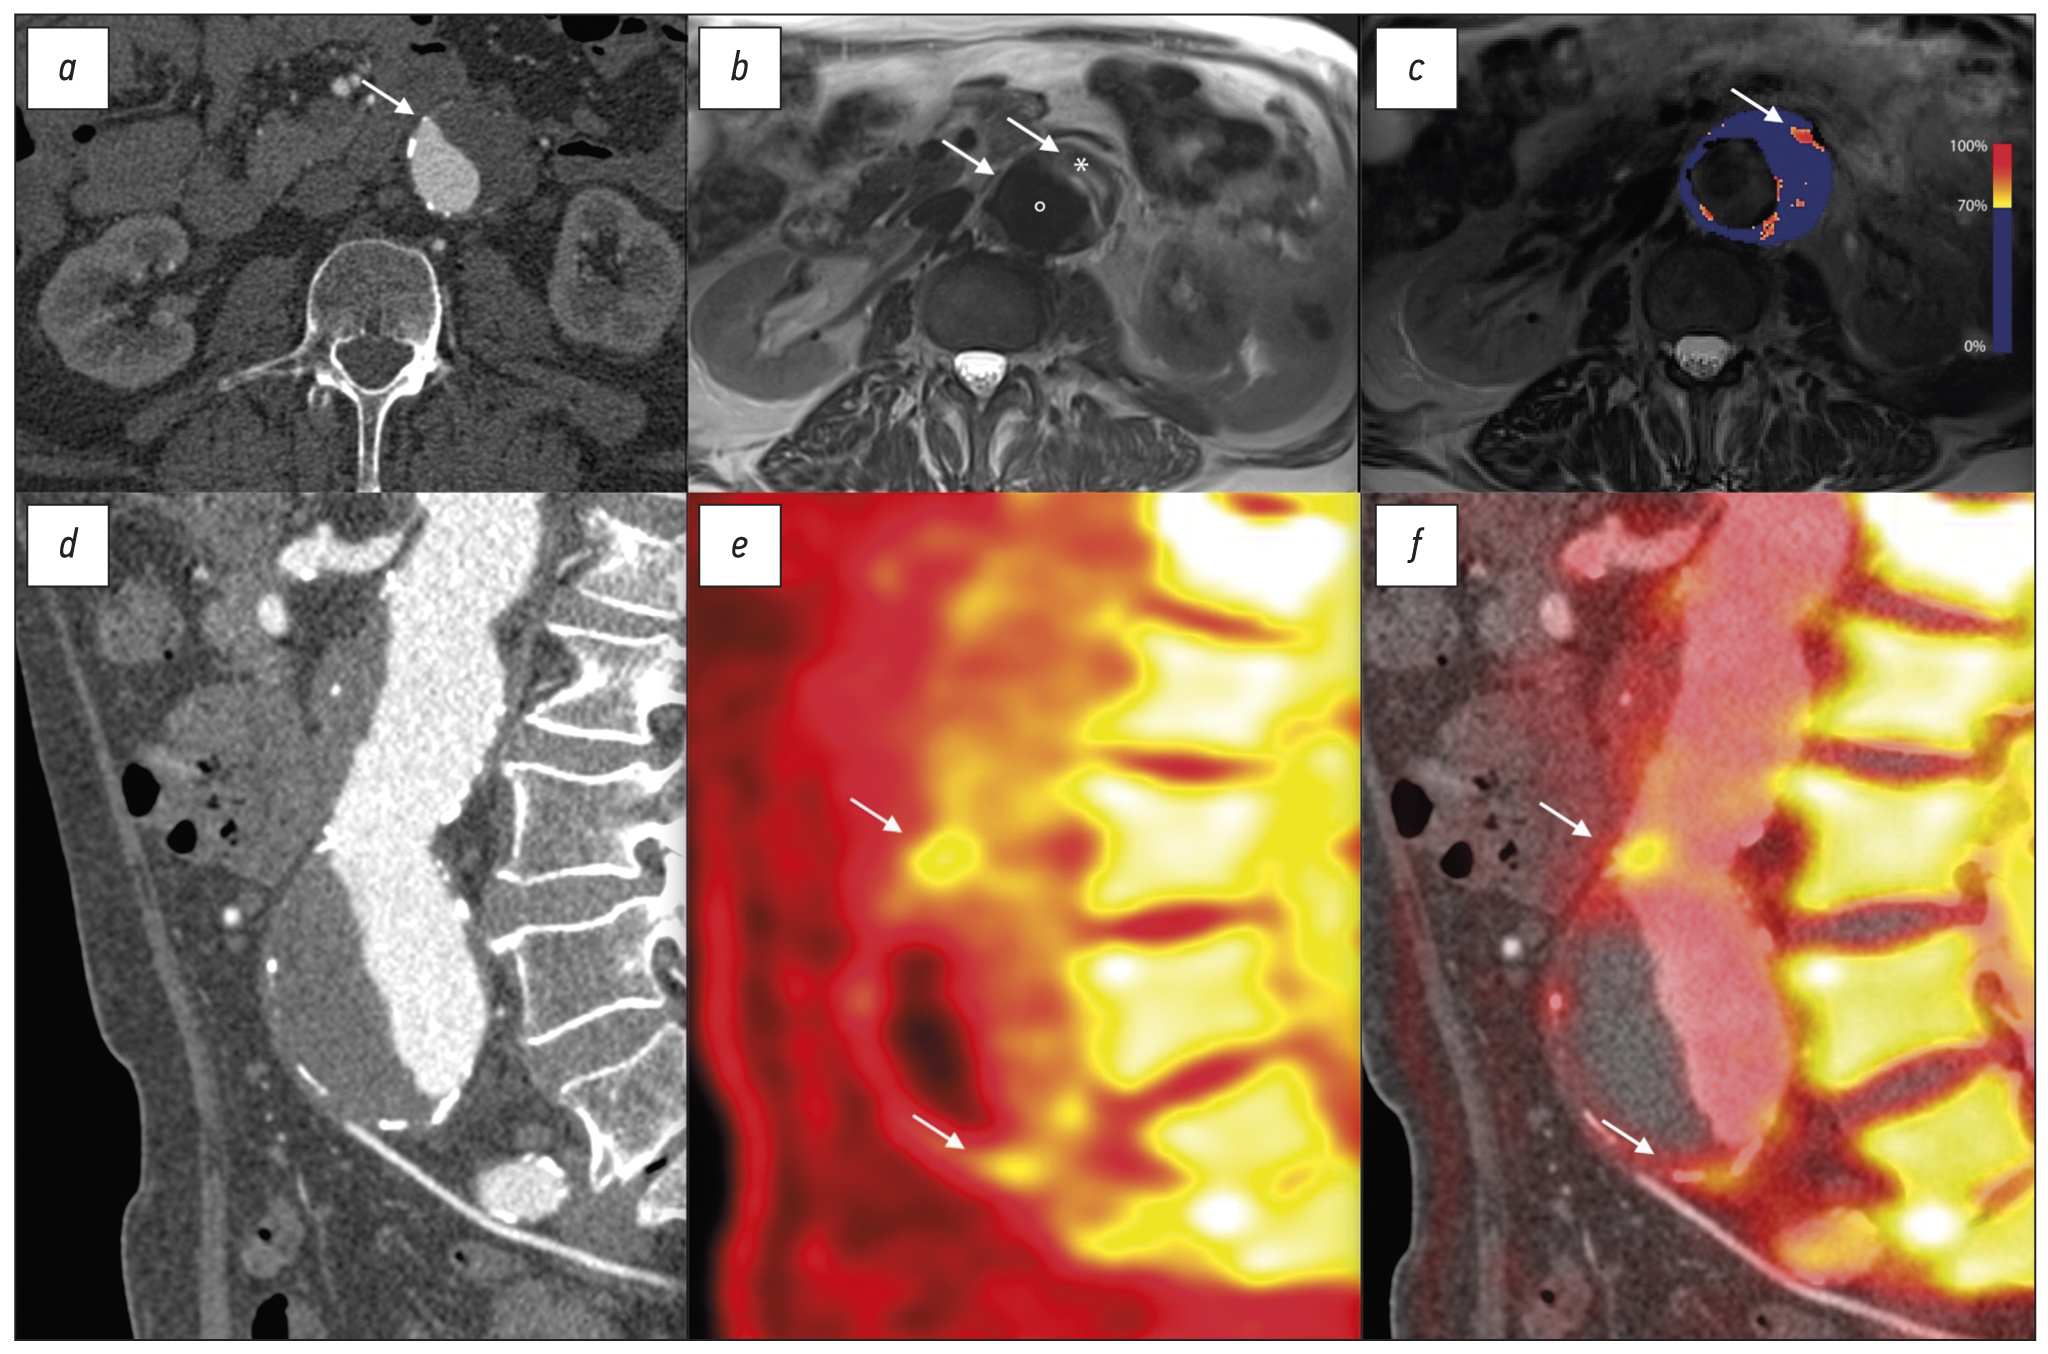

“Smart” Contrast Agent MRI

Ultrasmall paramagnetic particles of iron oxide (USPIOs) are 30 nm iron oxide nanoparticles stabilized with low-molecular-weight dextran. USPIOs accumulate in macrophages following phagocytosis and remain in the circulation for extended periods.47 Areas rich in USPIO-positive macrophages have a low-signal intensity on T2 and T2* weighted MRI.48 In the carotid arteries, USPIO accumulation within atherosclerotic lesions coincides with active plaque disease. These plaque exhibit intense macrophage infiltration.49 USPIO also accumulate with high affinity in areas of macrophage infiltration within abdominal aortic aneurysms (Figure 3C).50 Using smart MRI contrast agents to detect cellular activity within the vascular bed carries immense promise. These techniques may ultimately lead to the detection of active plaques at risk of imminent events and allow preventative therapy.

Fig. 3. Computed tomography (CT), magnetic resonance imaging (MRI) and positron emission (PET) tomography in a patient with juxta nal aneurysm of the abdominal aorta.

(A) Transverse view of the aneurysm as seen on CT shows a dilated aorta with thrombus. (B) T2 weighted MRI of the same aorta differentiates between the lumen (•), thrombus (*) and adjacent structures. (C) A parametric map of the difference in T2* MRI intensity before and after the administration of ultrasmall particles of iron oxide uptake shows high focal uptake in the anterior wall of the aneurysm (arrow). (D) The sagittal CT view delineates the morphology of the aneurysm. (E) 18F-Sodium fluoride PET shows uptake within the anterior aortic wall (arrows) detects areas of greatest vascular injury. (F) Superimposing PET over the CT confirms high 18F-Sodium fluoride uptake at the aneurysm neck and near the bifurcation (arrows). PET, positron emission tomography

The application of 18F-NaF PET/CT extends to vascular calcification in the wider arterial tree. In a prospective study of 72 patients with abdominal aortic aneurysms, there was marked uptake of 18F-NaF within the wall of aneurysms compared to non-aneurysmal sections and the aorta of healthy controls. High 18F-NaF uptake suggested weakening of the aortic wall and greater aneurysm expansion or rupture.70 These findings draw a link between metabolically active abdominal aortic aneurysms and morphological disease progression.

Smart contrast agents such as USPIO can further characterize biological activity within the aneurysm wall. High aortic mural USPIO uptake localizes to areas of macrophage infiltration and reflects vessel wall inflammation. An increased burden of USPIO uptake is observed in aneurysms with faster rates of expansion.48 In aneurysmal disease, 18F-NaF PET/CT detects aortic microcalcification. This is a common end point of multiple pathological processes ultimately leading to aortic degeneration. Increased 18F-NaF uptake is associated with faster aneurysm growth and an increased risk of rupture or requiring repair, independent of aneurysm diameter.70